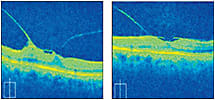

OCT Evaluation: OD-VMT (left) OD-VMA (right)

THE ANSWER

If you diagnosed this patient with VMT OD and VMA OS, you are correct! His aniseikonia was due to VMT OD. Retinal photos and SD-OCT were obtained. He was educated on the finding, given a home Amsler grid and advised to return in six weeks. At this visit, his symptoms improved, vision was unchanged, and OCT imaging showed no change in the macula. He is monitored every three months and remains stable. OM